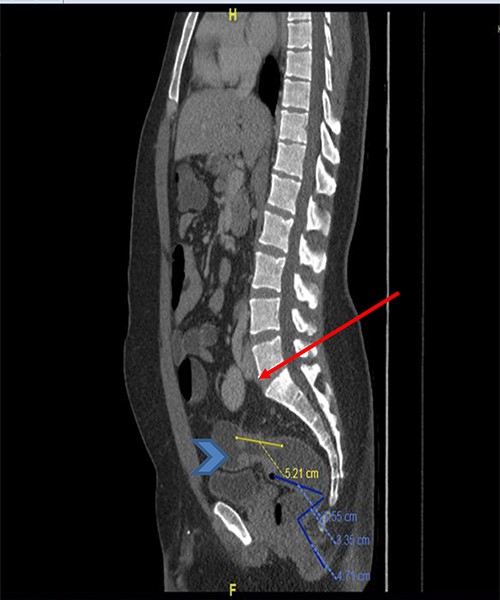

The basic lab Investigation showed Hgb level of 8.6 g/dL and CEA level of 4.8 ng/ml. On further investigation, colonoscopy revealed a large friable fungating circumferential rectal mass at 9 cm from anal verge extending to the distal sigmoid colon, it was nonobstructing with a length of 8 cm and the rest of the colon was normal. A biopsy from the mass was taken and showed invasive moderately differentiated adenocarcinoma. On further routine of radiological staging, CT of the chest, abdomen and pelvis confirmed the upper rectal mass with ectopic malrotated left kidney located in the lower abdomen and upper pelvis, opposite to L5-S1 vertebral bodies (Figs 1 and 2). There was no peritoneal disease or distant metastasis. Moreover, MRI pelvis showed again an upper rectal mass with mesorectal fat invasion and multiple lymph nodes (T3N2) and confirmed an ectopic left kidney (Figs 3 and 4).

CT scan of the abdomen and pelvis (sagittal view) showing the upper rectal mass (arrowhead) with ectopic kidney (arrow).